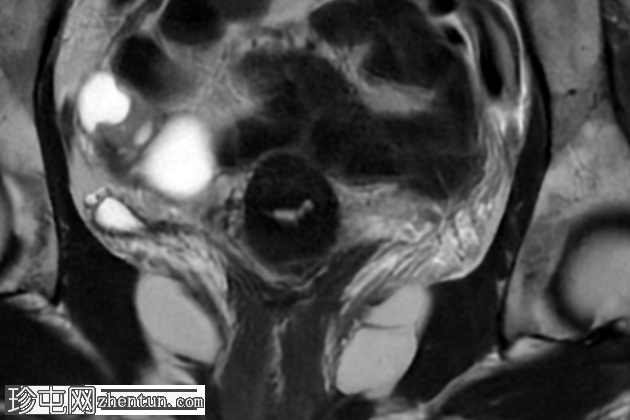

轴位T1加权像

脂肪抑制像

盆腔MRI显示右侧卵巢解剖位置可见一边界清晰的卵圆形肿块。该病灶由囊性和实性成分组成。囊性部分壁薄,在T2加权像上呈均匀高信号,在T1加权脂肪抑制序列上呈低信号,无对比剂增强。该实性成分的信号特征与正常卵巢组织相似,DWI成像未见扩散受限,静脉注射造影剂后未见异常强化。

此外,在子宫左侧壁可见一管状薄壁囊性结构,延伸至同侧髂外血管,末端呈盲端。该结构在T2加权像上呈均匀高信号,在T1加权脂肪抑制序列上呈低信号,且无造影剂强化。

本例中,盆腔MRI显示,患者右侧卵巢解剖位置存在一个边界清晰的附件肿块,该患者有20年前行双侧输卵管卵巢切除术的病史。该病灶包含囊性和实性成分,其中实性部分表现出与正常卵巢组织相似的信号特征。无扩散受限和无可疑的增强扫描强化提示排除恶性病变。这些影像学特征结合相关的手术史进行解读,符合残留卵巢组织的特征,支持卵巢残留综合征的诊断。此外,还发现对侧子宫左侧延伸出一个管状薄壁囊性结构,末端呈盲端。其形态、信号特征和无强化表现符合输卵管残端或输卵管残端积水,这是输卵管切除术后常见的术后表现。附件残余的存在进一步支持术后病因,而非原发性妇科肿瘤

主要鉴别诊断包括腹膜包涵囊肿、子宫内膜异位症相关囊肿和附件肿瘤。腹膜包涵囊肿通常位于腹膜腔内,不含类似卵巢组织的实性成分。子宫内膜异位囊肿通常在T1加权像上表现为高信号,T2加权像上出现阴影,并具有其他特征性MRI表现,而本例4中均未见这些表现。鉴于无扩散受限、无可疑强化以及实性成分的良性影像学表现,肿瘤性病变的可能性较小。